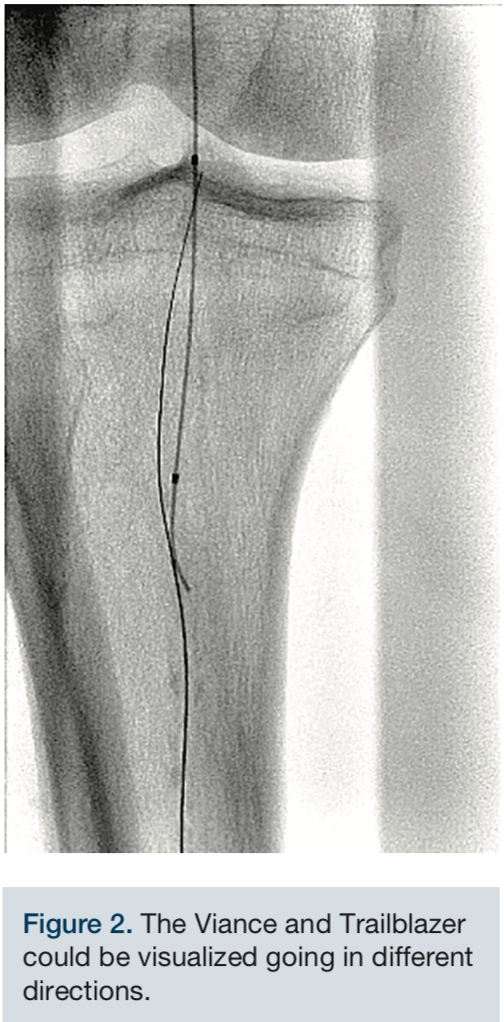

image